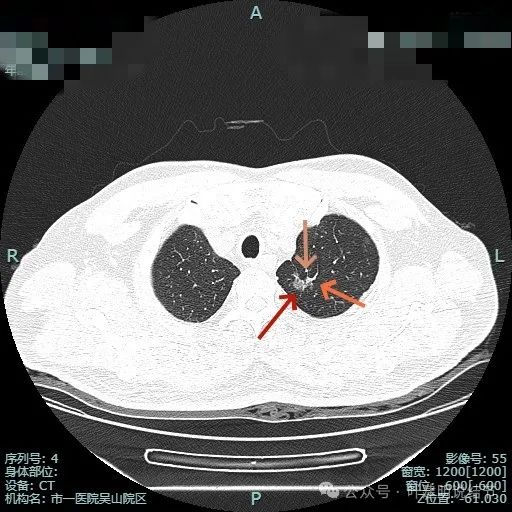

先看非薄层影像:

有血管异常增粗与进入,边缘有细毛刺征。

血管穿行与表面浅分叶。